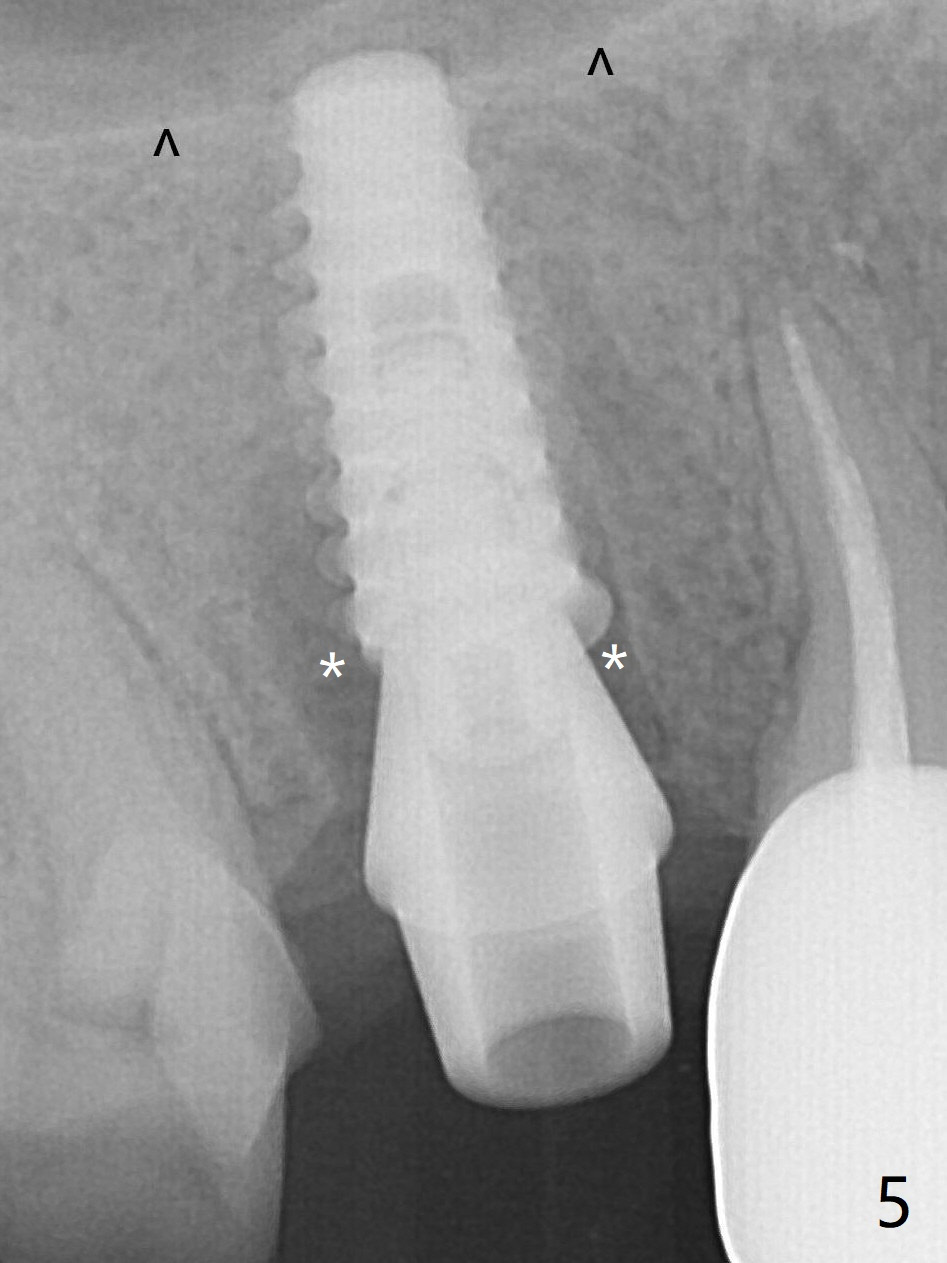

To reduce the gap and periimplantitis, a 5x11 mm IBS implant is placed with insertion torque > 50 Ncm after further osteotomy using Magic Drills (Fig.5). In fact the implant is placed too deep (as compared to Fig.3). Following placement of 5.5x4(4) mm abutment, a splinted provisional is fabricated at #3 and 4. An abutment with 5 or 6 mm cuff is needed. ^: sinus floor. The peri-implant gaps (Fig.5 *) seem to disappear (Fig.6) with the help of bone graft. Impression is taken 4.5 months postop (Fig.8,9).